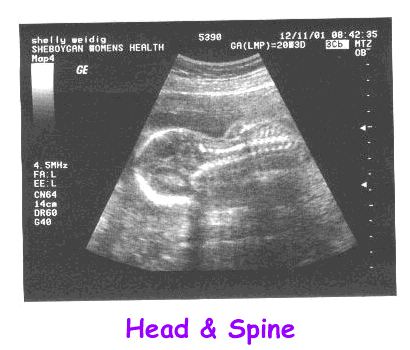

Pictures taken December 11, 2001

at the age of 20 weeks, 3 days